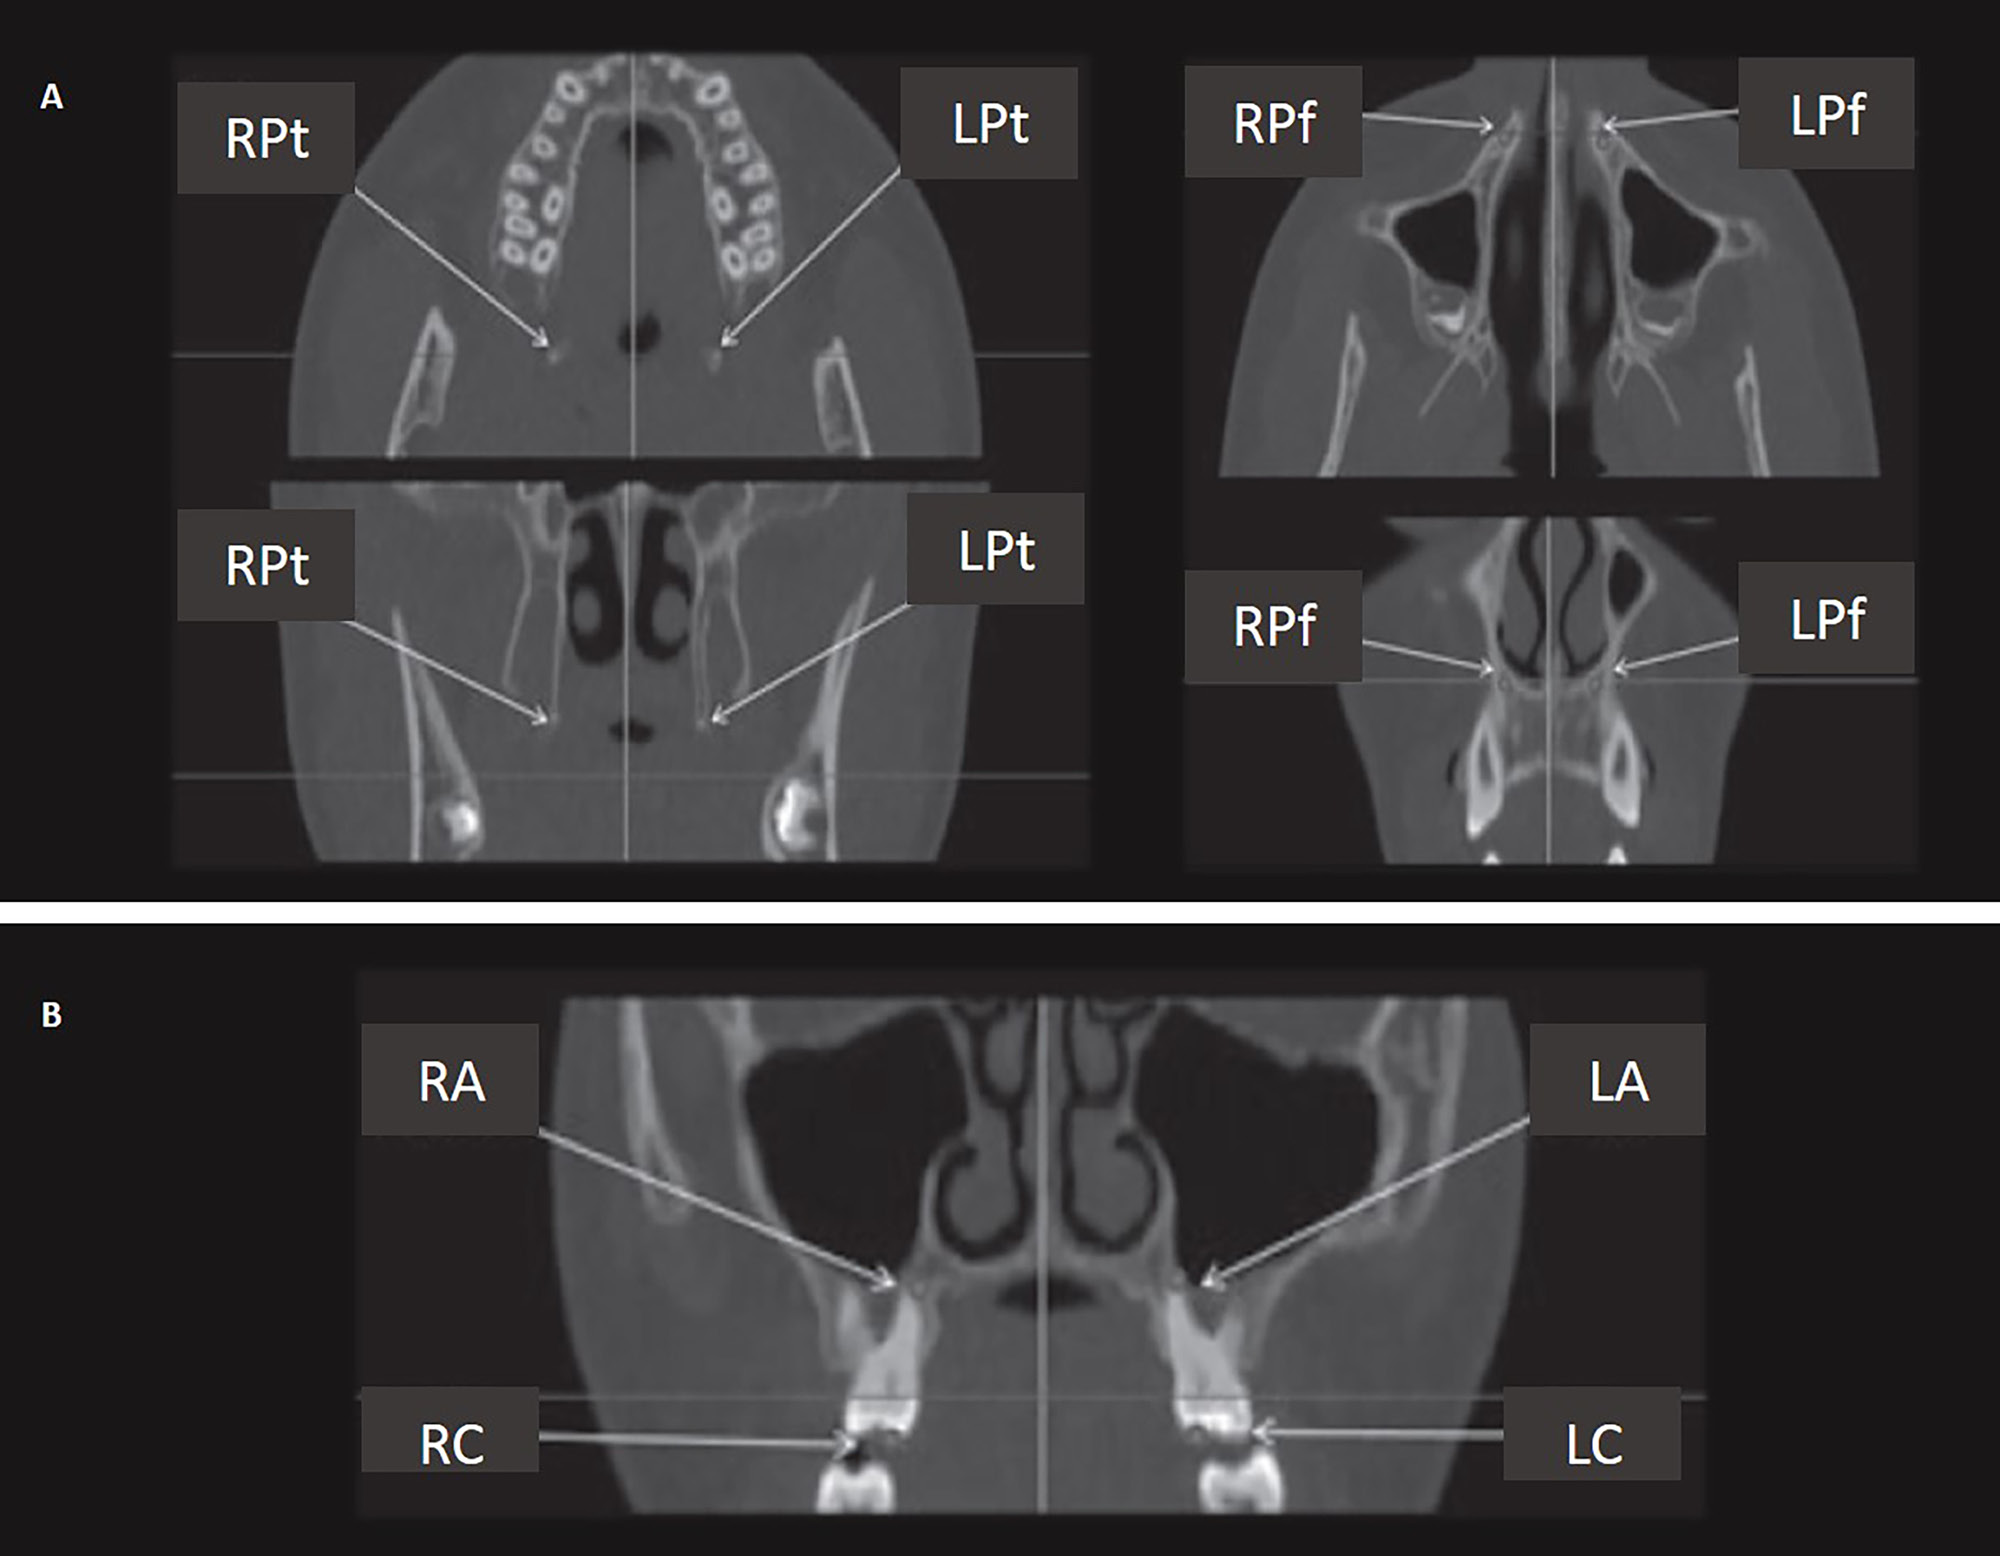

To ensure the appropriate position of the patient’s head, it was oriented in such a way that the Frankfurt plane was parallel to the horizon. The imaging system SCANORA® 3D (Soredex, Tuusula, Finland) was used (amperage: 12.5 mA; voltage: 90 kV; voxel size: 0.25 × 0.25 × 0.25 mm3; mean scanning time: 20 s). Two CBCT images were taken at the following time points: before expansion (T1); and 3 months after expansion and the removal of the appliance in the RME group, and 1 month after expansion and the removal of the appliance in the SME group (T2). Eight landmarks were identified on CBCT images: 4 skeletal landmarks (right/left pterygoideous point and right/left piriform point); and 4 dental landmarks (right/left root apex and right/left cusp tip) (Table 1).5 Four skeletal measurements were made: anterior palatal width; posterior palatal width; palatal width at premolars; and palatal width at molars (Table 1).5, 15 Six dentoalveolar measurements were made: inter-premolar width at the root apex; inter-premolar width at the cusp tip; inferred premolar tipping; molar width at the level of apices; molar width at the level of cusps; and inferred molar tipping (Table 1).5 Figure 3 and Figure 4 demonstrate the landmarks and measurements used. The definitions were derived from studies by Martina et al.5 and Lin et al.15 Both ‘inferred’ premolar and molar tipping measurements were given in millimeters (i.e., they were linear measurements), although they indirectly represented the amount of change in the buccolingual inclination of premolars and molars.5